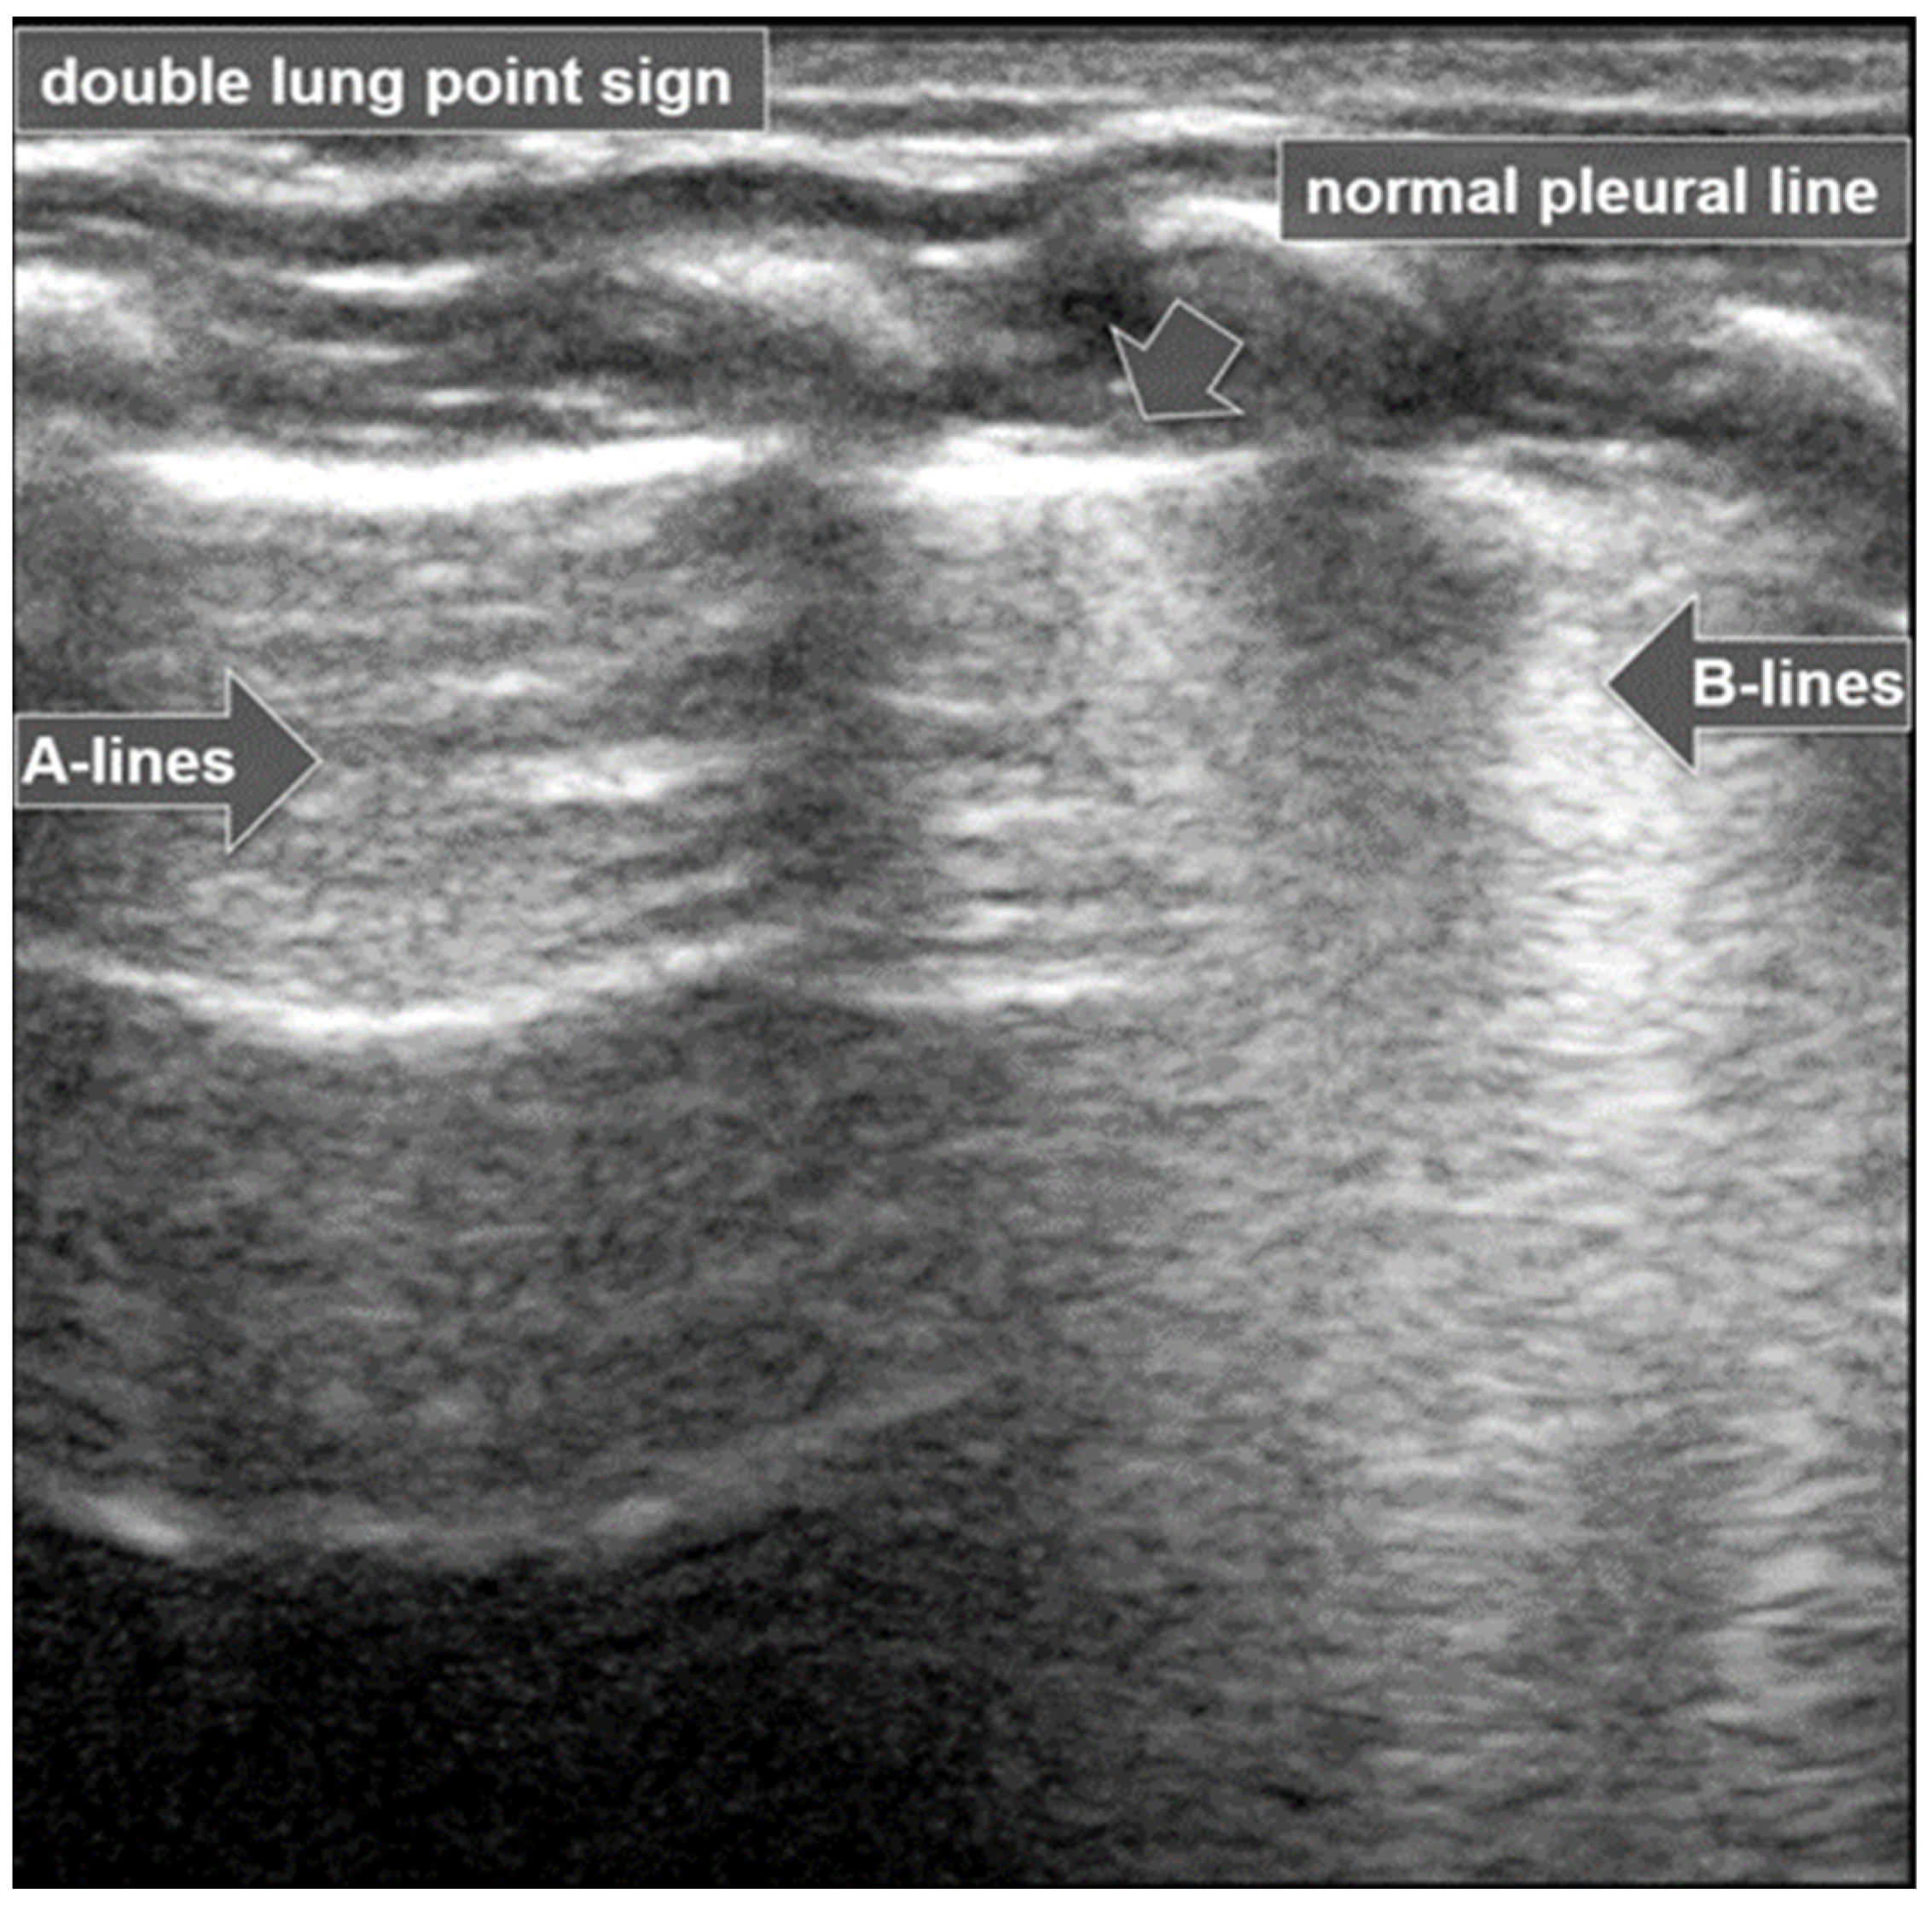

3.1.8. Double-Lung-Point Sign

The “double-lung-point sign” is a sharp sonographic demarcation visible between normally aerated upper lung fields and lower lung zones, with multiple and/or confluent B-lines indicative of interstitial edema (Figure 9).

Figure 9.

Double-lung-point sign: Normally aerated upper lung fields (arrow) and lower lung zones with multiple confluent B-lines (open arrow).

This pattern is characteristic of Transient Tachypnoea of the Newborn (TTN) [27,28], where a marked difference in lung echogenicity between superior and inferior regions can be visualized by ultrasound [6,26]. This finding has been reported to have a specificity of up to 100% for TTN [6,17,26], and is not typically present in other neonatal pulmonary conditions such as atelectasis, pneumothorax, pneumonia, or pulmonary hemorrhage [17,29].